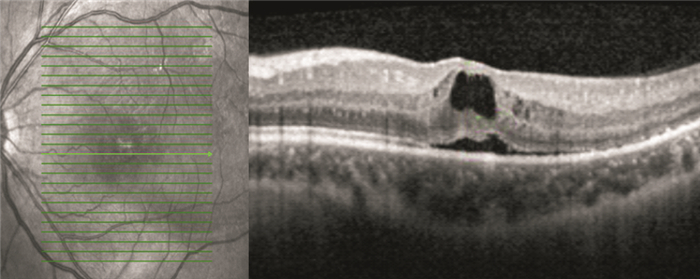

OCT檢查發現,手術后視網膜下液吸收時間1~13個月,平均視網膜下液吸收時間(7.82±3.52)個月。手術后12個月,42只眼中,視網膜下液吸收37只眼,占88.1%;視網膜下液殘留5只眼,占11.9%。視網膜下液吸收37只眼中,視網膜微結構正常15只眼;神經上皮層黃斑囊樣水腫5只眼(圖 1);光感受器內外節連接(IS/OS)斷裂12只眼;IS/OS和外界膜(ELM)斷裂5只眼(圖 2)。

患眼OCT像。神經上皮層黃斑囊樣水腫

患眼OCT像。神經上皮層黃斑囊樣水腫

OCT檢查發現,手術后視網膜下液吸收時間1~13個月,平均視網膜下液吸收時間(7.82±3.52)個月。手術后12個月,42只眼中,視網膜下液吸收37只眼,占88.1%;視網膜下液殘留5只眼,占11.9%。視網膜下液吸收37只眼中,視網膜微結構正常15只眼;神經上皮層黃斑囊樣水腫5只眼(圖 1);光感受器內外節連接(IS/OS)斷裂12只眼;IS/OS和外界膜(ELM)斷裂5只眼(圖 2)。

患眼OCT像。神經上皮層黃斑囊樣水腫

患眼OCT像。神經上皮層黃斑囊樣水腫